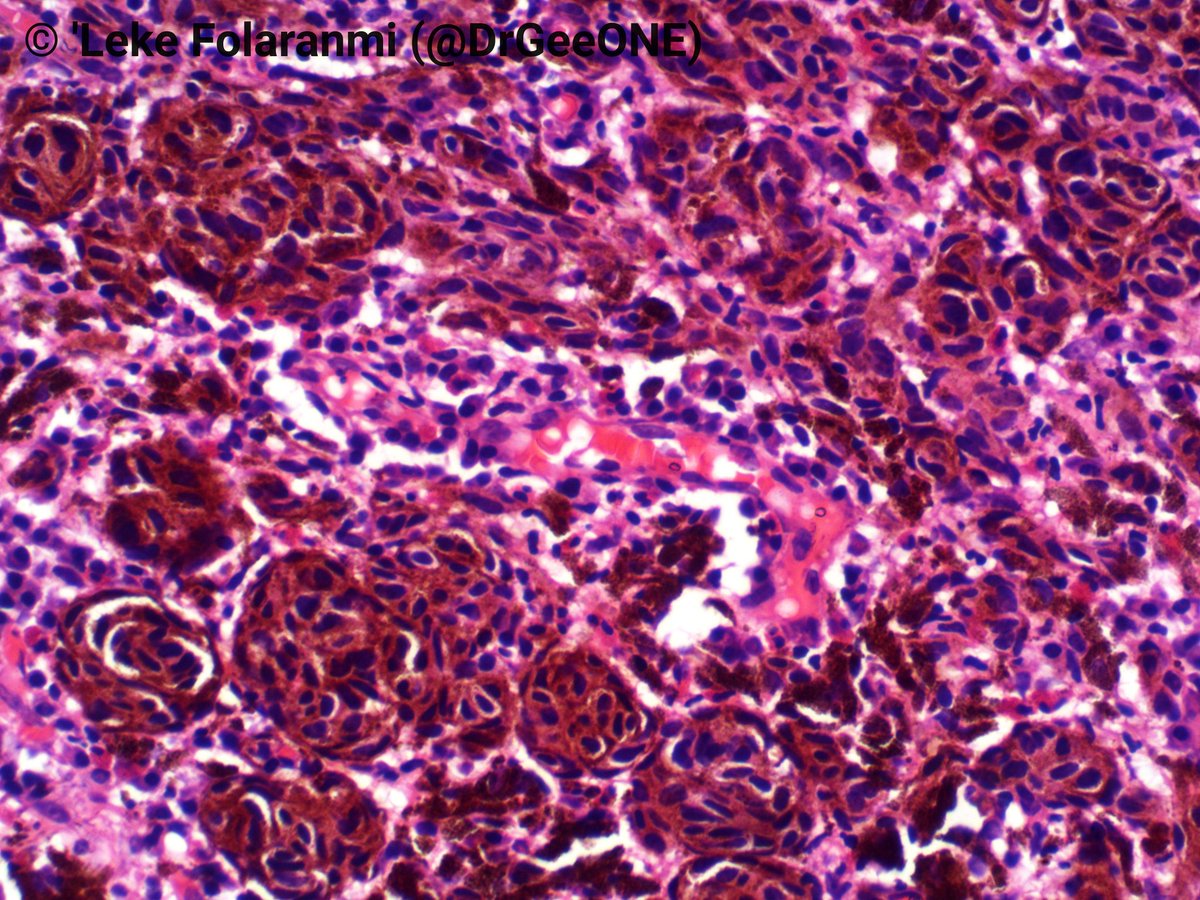

Here's a nice example of an epithelioid choroidal melanoma for your